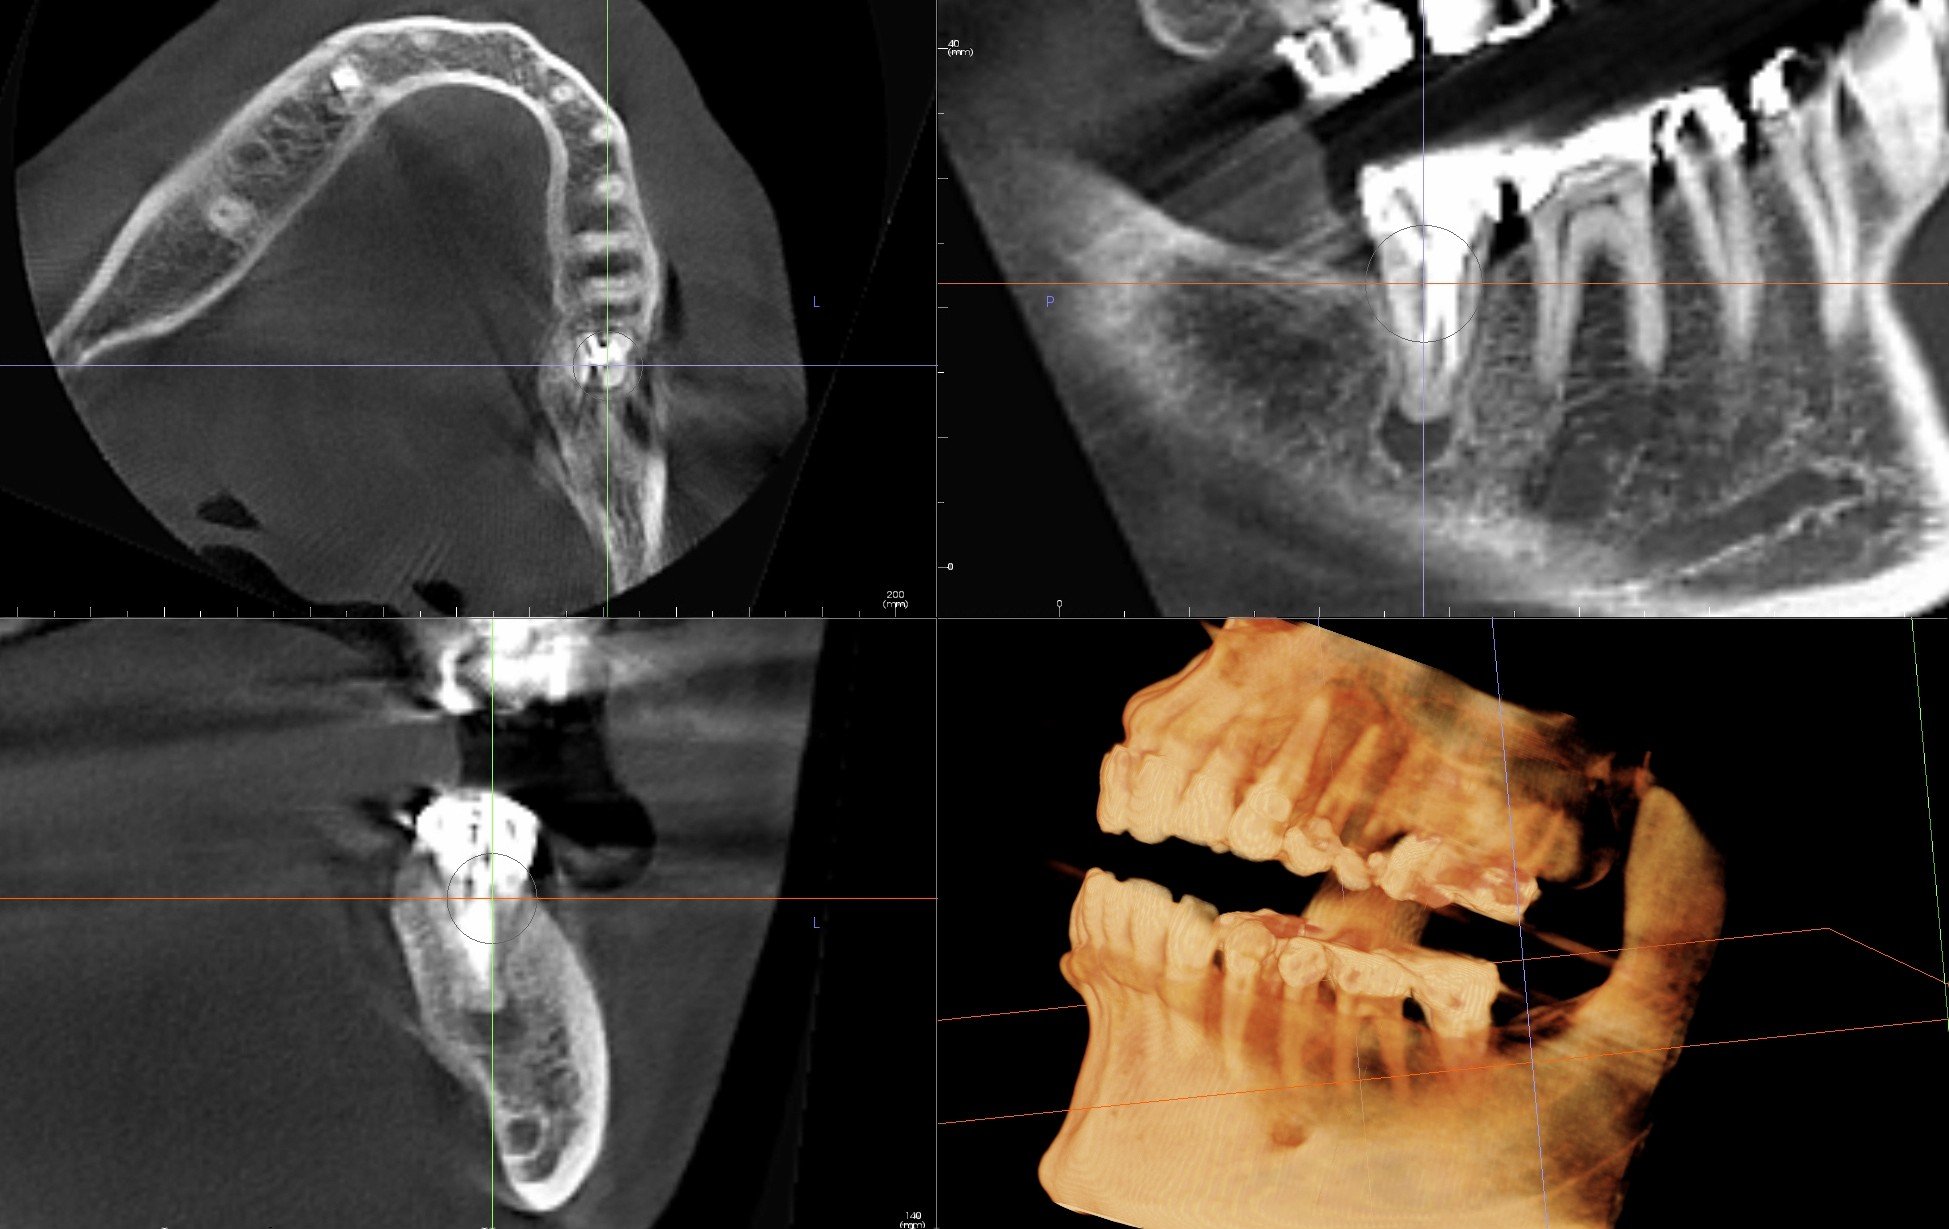

From oralradiologytoronto.ca

CBCT Scan For Failed Root Canal Oral Radiology Toronto Failed Root Canal Reddit A user shares their experience of having a root canal fail and causing an abscess in their face. For the past three months i have been undergoing problems with an upper left molar. Other users and a dentist offer. A failed root canal is when your treated tooth experiences some type of complication. I’d two root canals start to fail. Failed Root Canal Reddit.